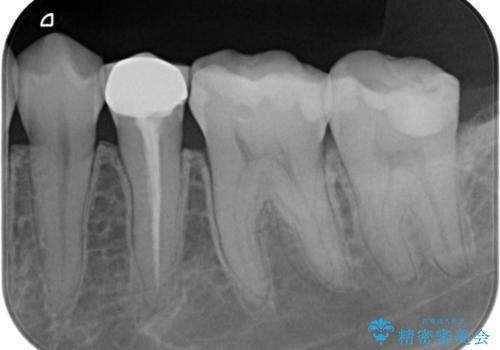

- 奥歯に虫歯があると言われて治療された患者様です。

何度か同じ歯に保険治療で治したそうですが、欠けたり再度う蝕になってしまった経験から自費治療を希望され、丈夫でキレイなセラミッククラウンにて治療いたしました。